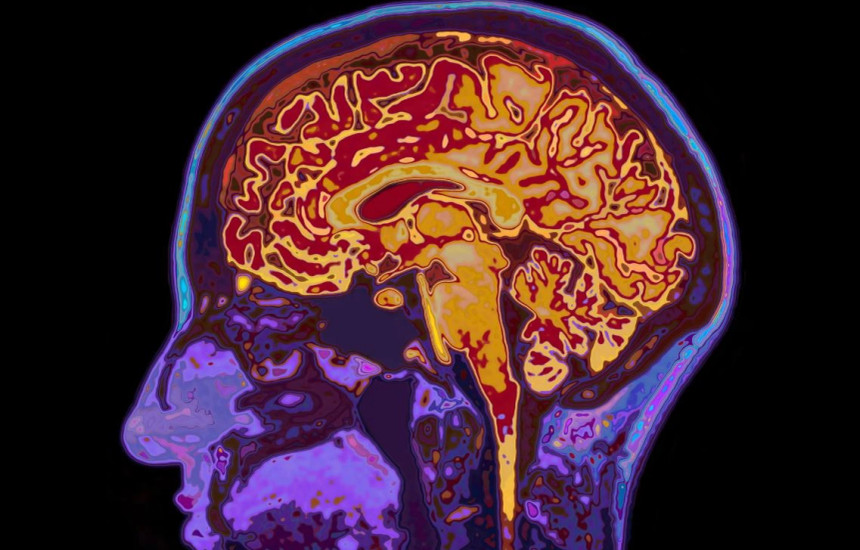

truri